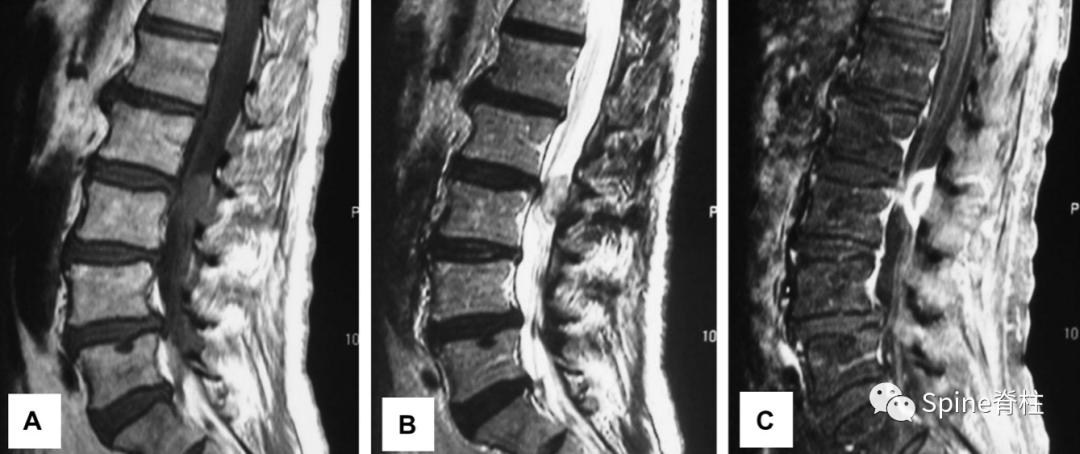

腰椎间盘突出症状表现,腰椎间盘突出症疼痛最佳止痛方法

发表在顶级四大医学期刊之一的NEJM的最经典病例:患者为29岁女性患者,因“右小腿疼痛、感觉异常”就诊,大小便正常。起始腰椎磁共振提示腰4-5椎间盘突出并椎管狭窄,神经根压迫严重(左图)。她选择保守治疗,5个月后,复查腰椎磁共振惊奇的发现突出的椎间盘被吸收了,且临床症状完全缓解。

但既往文献报道腰椎间盘突出自发性重吸收的文献,多为病例报道,从证据等级角度来说,是低级别证据,相对参考可信度低(举个不恰当的例子,就好比天气预报明天会不会下雨?中央电视台预报的可信度相对高些,但县级天气预防的可信度就低些了,而文献中报道的腰椎间盘突出自发性重吸收的文章证据等级属于县级天气预报水平)。

另外,从另一个角度来说,腰椎间盘突出重吸收发生率是很低的,也就是大部分腰突是不会发生重吸收的。 因此,我们不能把所有赌注都压在小概率的“重吸收”上。